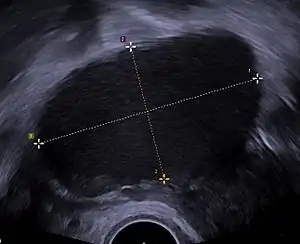

A health history and a physical examination can lead the health care practitioner to suspect endometriosis. There is a clear benefit for performing a transvaginal ultrasound (TVUS) as a first step of testing for endometriosis.[86]

Ultrasound

Vaginal ultrasound can be used to diagnosis endometriosis, or for localizing endometrioma before surgery.[101] This can be used to identify the spread of disease in individuals with well-established clinical suspicion of endometriosis.[101] Vaginal ultrasound is inexpensive, easily accessible, has no contraindications and requires no preparation.[101] By extending the ultrasound assessment into the posterior and anterior pelvic compartments a sonographer is able to evaluate structural mobility and look for deep infiltrating endometriotic nodules.[102] Better sonographic detection of deep infiltrating endometriosis could reduce the number of diagnostic laparoscopies, as well as guide disease management and enhance patient quality of life.[102]